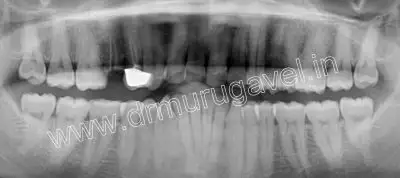

Radiographic examination

- OPG and CBCT taken.

- CBCT shows periodontal widening and gp short of apex in relation to 24 region..

- Sufficient bone height and width was present in relation to 24 and 25 region to place implants..